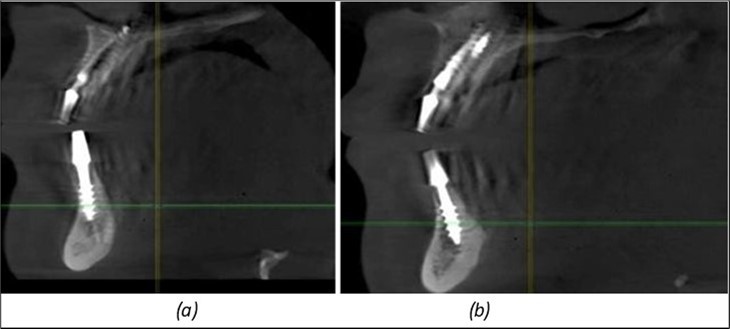

Figure 14.Rx panoramic final situation control: (a) Panoramic X-ray with the addition of a distal BCS implant in quadrant 3 at 11.2022; (b) Control X-ray, 10.2023.

The results of rehabilitation treatment with corticobasal and compressive implants with a polished surface after the failure of two stage implants were highlighted over a period of 3 years and 3 months as being very good (Figure 14, Figure 15), with the patient completing a satisfaction survey in this regard. Certainly, it is necessary to continuemonitoring these results in the long term.